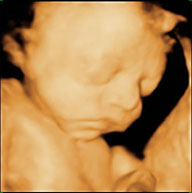

3D或4D胎兒寫真是E世代懷孕準媽媽的新興服務,目前已非常普及方便。就像結婚拍婚紗,懷孕中的年輕夫妻流行為自己肚子裏愛的結晶留下最早的永恆記錄。本院婦產科目前擁有『旗艦級4D動態實時立體彩色超音波』,可讓準爸媽直接從不同的角度,觀察寶寶栩栩如生的模樣,對缺乏醫學解剖觀念的廣大孕婦,提供最直接的了解,並藉由光碟記錄胎兒影像,留作父母與小寶貝的紀念。這些4D影像是傳統超音波所無法提供的不同於一般產檢,非屬一般醫療診斷行為,更無法取代傳統胎兒超音波篩檢。4D影像要好看,必須有足夠羊水,因此這類4D胎兒寫真適合拍攝時間約在24~30週之間,週數太大羊水相對變少,姿勢易固定在同一位置,且容易被自己身體其他部分擋住;週數太小時,影像細節抓不到,容貌較不好看。

有些媽媽會質疑自己得到的影像沒有別人漂亮,或是為何每次得到的效果都不一樣?其實這跟孕婦本身肚皮超音波穿透力、羊水量及寶寶的位置有關。不同的孕婦因不同的條件,得到的影像自然清晰度不同,但不會有漂亮與否的差異,因為每個媽咪的寶寶都是最可愛的。即使同一位媽咪在不同時間做3D寫真,會因當時寶寶及孕婦情況可能完全有不同的效果。如果當時條件不好,通常會請媽咪去走一走,吃點東西,讓寶寶換個位置再照,如果還是不行只好換時間再做,偶爾會遇到跑好幾次的情形,可能要有耐心,最好前一晚先與他溝通,說不定他心情好,在照的當天會多多配合呢!

3D胎兒影像寫真